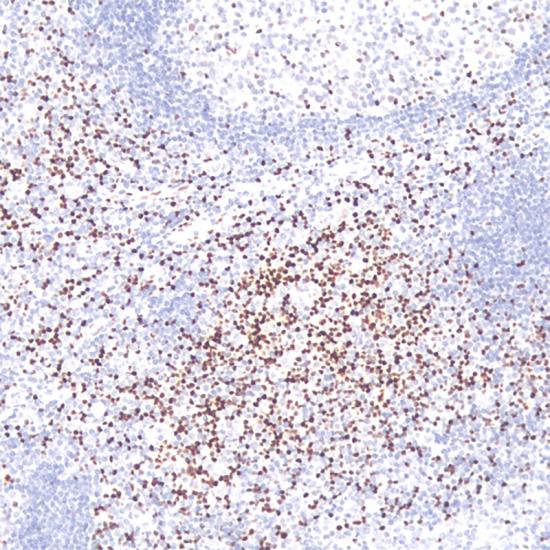

LEF1是一種核轉(zhuǎn)錄因子,調(diào)控細胞增殖及存活,正常表達于T細胞及前B細胞,而在成熟B細胞中不表達。LEF1在幾乎所有CLL/SLL中過度表達,不表達其它小B細胞淋巴瘤。

• 陽性部位:

細胞核

• 陽性對照:

扁桃體